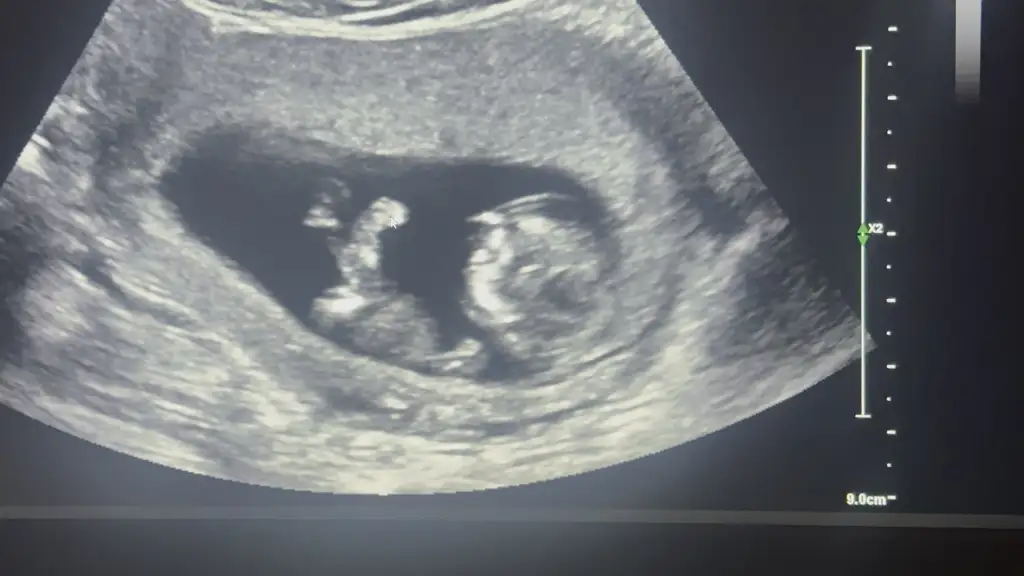

oyyy bana kız gibi geldi doktor ne söylediiEki Görüntüle 3676721 Cinsiyet tahmini yapar mısınız bana daDoktorumuz %80 olarak tahminde bulundu, bugün de fetal dna verdik haftaya kesinleşecek

Ay maşallah kız gibi geldiEki Görüntüle 3676721 Cinsiyet tahmini yapar mısınız bana daDoktorumuz %80 olarak tahminde bulundu, bugün de fetal dna verdik haftaya kesinleşecek

Erkek gibi geldi bana kuzumEki Görüntüle 3676721 Cinsiyet tahmini yapar mısınız bana daDoktorumuz %80 olarak tahminde bulundu, bugün de fetal dna verdik haftaya kesinleşecek

Doktor ne dediiiiiiiiiEki Görüntüle 3676721 Cinsiyet tahmini yapar mısınız bana daDoktorumuz %80 olarak tahminde bulundu, bugün de fetal dna verdik haftaya kesinleşecek

oyyy bana kız gibi geldi doktor ne söyledii![]()

Ay maşallah kız gibi geldi![]()

Teşekkürler kızlarrErkek gibi geldi bana kuzum

Daha mı kesin bir sonuç elde ediliyor ? Ve ne kadar fiyatıİkili üçlü dörtlü testleri vermek istemedik. Fetal dna içinde bütçe ayırmıştık çok şükür o yüzden direkt fetal dna verdikEnse kalınlığı, burun kemiği normal çıktı

Bu arada sonucunuz güzel çıkmış tebrik ederimİkili üçlü dörtlü testleri vermek istemedik. Fetal dna içinde bütçe ayırmıştık çok şükür o yüzden direkt fetal dna verdikEnse kalınlığı, burun kemiği normal çıktı